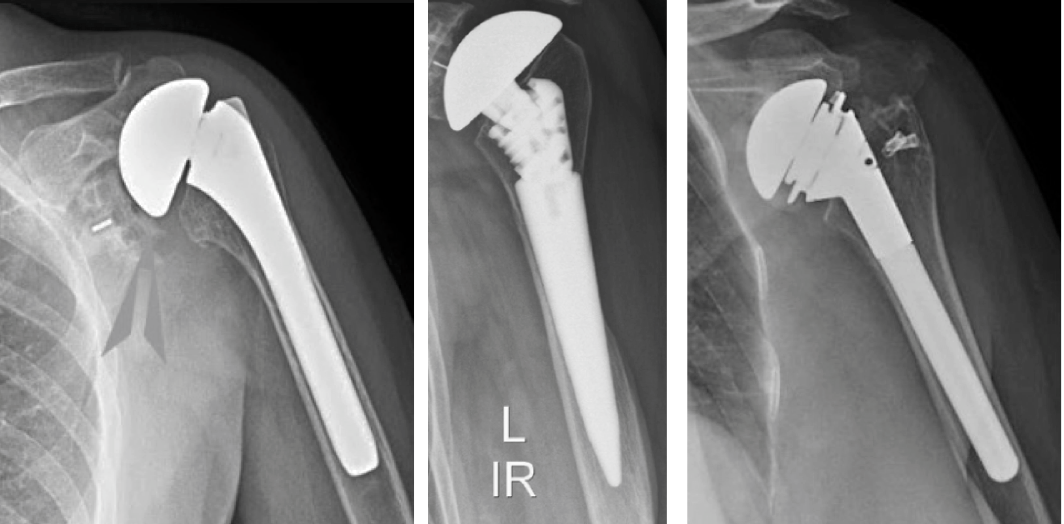

Total shoulder arthroplasty, also known as total shoulder replacement, is a surgical procedure that replaces both the damaged ball (humeral head) and socket (glenoid) of the shoulder joint with artificial components. At our Delhi orthopedic center, our experienced surgeons use advanced implants and precision techniques to restore joint mobility, eliminate pain, and help patients return to their normal activities.

This procedure is performed to treat severe shoulder arthritis, joint degeneration, or injury when non-surgical treatments are no longer effective. The damaged parts of the shoulder joint are replaced with smooth, durable prosthetic components that mimic the natural anatomy of the shoulder.